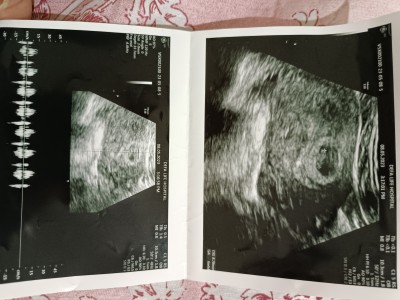

İyi geceler hanımlar bu gün ilk defa bebeğimin kalp atışını duydum normal de 7+1 demişti doktorum ama ultrasona bakınca geri 6+1 dedi sorum şu ki paylaştığım ultrason görüntüsünde ki yazılar nedir bileniniz var mı

Gebelik haftası 6+1

Üsttekinde CRL yazıyor sanırım bulanık tam çözemedim eğer ki öyle yazıyorsa baş ve popo arasındaki mesafenin kısaltması :)

Fl uzunluğu onu biliyorum bir tek. Geç döllenme olmuştur o yüzden 2 haftalık geri çıkar bebek bu önemli bir şey değil. Kalp atışını da duymuşsunuz demek ki sağlıklı. Hayırlı olsun